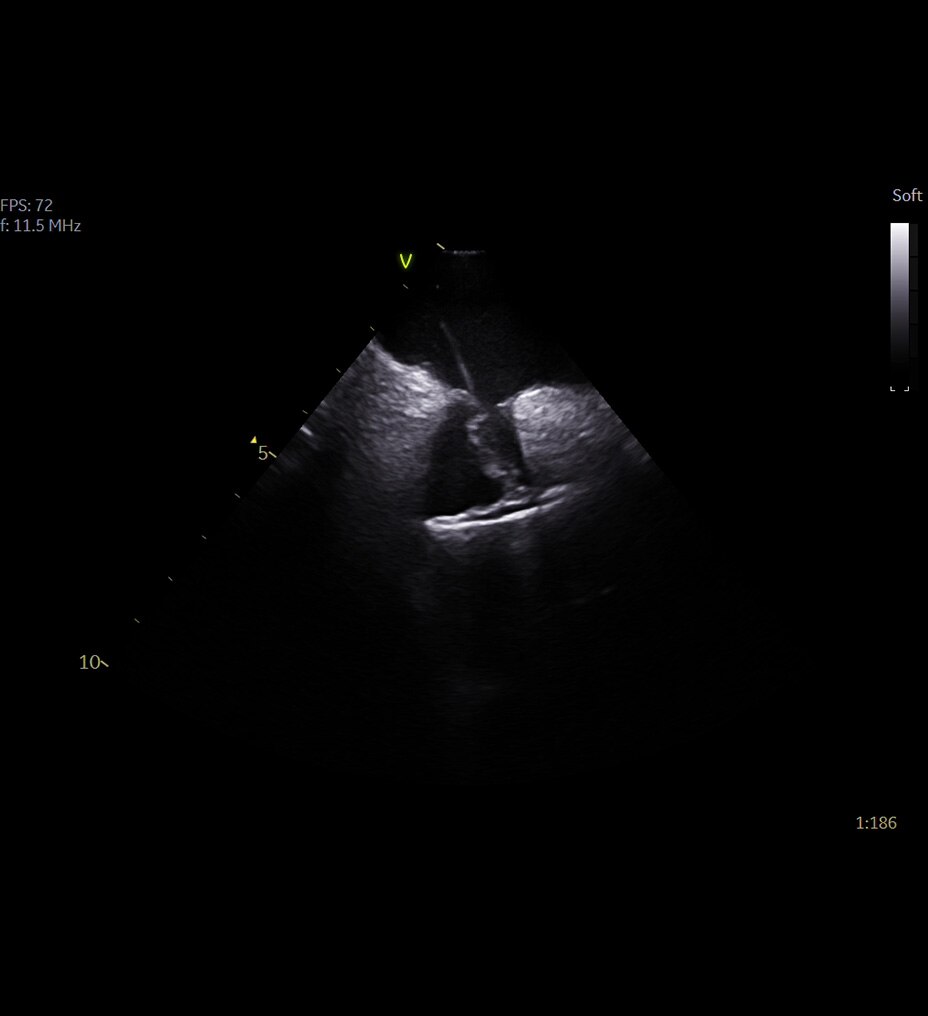

PRECISION NEEDLE GUIDANCE

Accurately guide and visualize injections

Even in the most experienced hands, blind injections—those performed without imaging—are not 100% accurate. By using ultrasound for needle guidance, the needle is highlighted and you have quality visualization of joints and soft tissue during procedures at a lower acquisition cost than other imaging modalities.